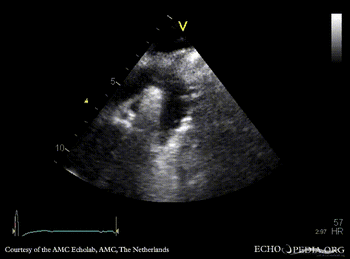

| Courtesy of: AMC Echolab, AMC, The Netherlands | |

| Suprasternal view | Suprasternal view with Color Doppler |